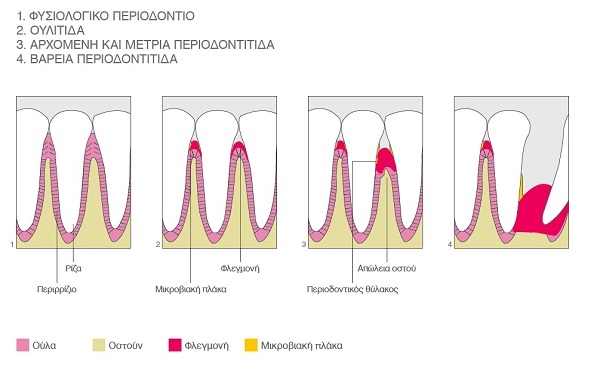

Periodontitis is one of the most serious dental diseases.

It is the progress of gingivitis, an inflammatory disease of the gums, which if not treated promptly develops into periodontitis. The inflammation extends from the gums to the bone that supports the teeth, which slowly subsides.

When periodontitis is not treated, more bone is lost, so progressively teeth start to move and finally they are extracted .